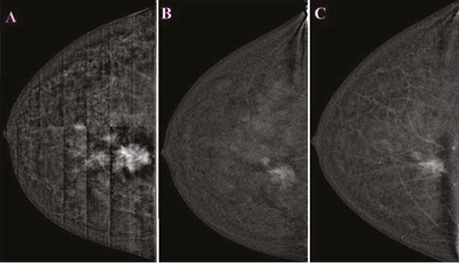

Проаналізувавши надані площинні мамографічні зображення, зазначено високу щільність паренхіми МЗ категорії ACR С з наявністю середньоінтенсивного гетерогенного ущільнення в ретромамарному просторі на 1 год правої МЗ розміром 27×21×22 мм з нечіткими променистими краями. Відзначалася наявність перинодулярної інфільтрації паренхіми, згущення структурного малюнку МЗ навколо вузлового компонента. У правій аксилярній ділянці лімфатичний вузол розміром 32×14 мм, кірково-медулярна диференціація простежується, кірковий шар нерівномірний, потовщений до 5,3 мм (рис. 1).

Рис. 1. Площинна мамографія в R-СС- та R-MLO-проєкціях. На 1 год ретромамарно — гетерогенне середньоінтенсивне вузлове новоутворення з нечіткими краями. У правій пахвовій ділянці лімфатичний вузол з нерівномірно потовщеним кірковим шаром